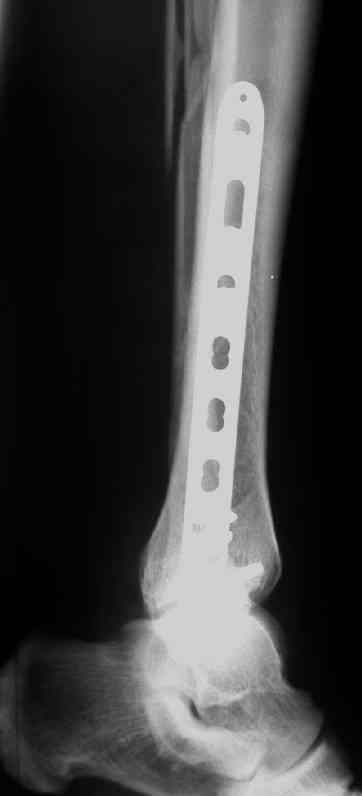

Выполнил MIPO предизогнутой метафизарной LCP

И все же немного критики:1) Вы добивались анатомичной репозиции, которая требует абсолютной стабильности, которая в свою очередь возможноа только в условиях межфрагментарной компрессии. Пластина уложена как мостовидная, не хватает стягивающнго винта. 2) есть укорочение малоберцовой кости, необхордимо восстановить ее длину! В таком виде я бы не стал разрешать раннюю нагрузку. Добавить самую малость: стягивающий винт и остеосинтез малоберцовой кости и больной может наступать сразу.

> есть укорочение малоберцовой кости, необхордимо восстановить ее длину

А Вы всегда оперируете м\берцовую кость? Здесь вроде г/стопный сустав напрямую незаинтересован.

М\б кость укорочена, а это создает предпосылки к вторичной вальгусной деформации даже с LCP, спросите у Виталия Дрягина.